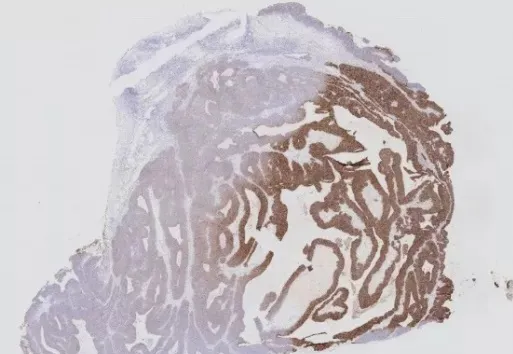

四、邊緣效應(yīng)

干片的原因有動作太慢、忘記滴液、滴液流失等,造成非特異性染色,即“邊緣效應(yīng)”(如圖4)。采用DAKO筆或PAP Pen在距離組織邊緣3-4 mm處畫圈,可達到有效的避免液體流失、提高操作速度的效果。

另外,向清洗緩沖液中加入吐溫20(Tween-20)也是一種防止干片的好方法。500ml PBS磷酸鹽緩沖液,加入2~3滴Tween-20即可。

圖4 邊緣效應(yīng)